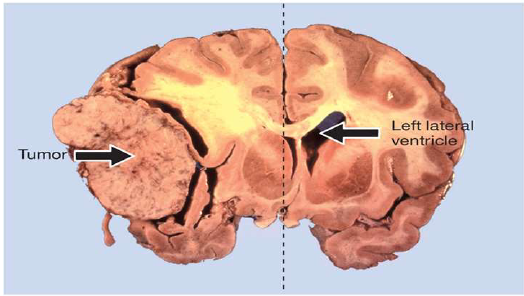

a mass of cells whose growth is uncontrolled and that serves no useful function

Can be malignant (cancerous) or benign –> Depends on whether the tumor is encapsulated

• Compression

• Infiltration

• Malignant can compress and infiltrate

• Benign tend to only compress